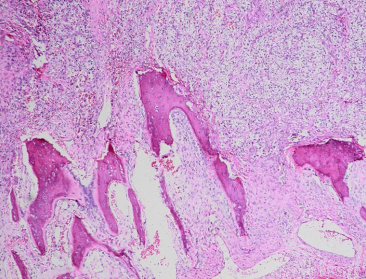

2例眼眶转移性CC-RCC中例4为女性,56岁,右眼红肿伴眼球突出2个月,2个月前外院行右肾CC-RCC切除手术,术前CT显示右眶外上方3 cm ×4 cm软组织肿块,涉及眶顶及外侧肌锥外与中颅底,伴眶顶壁、外侧壁与蝶骨大翼骨质破坏(图2 )。PET-CT提示右肾癌术区未见明显肿瘤复发,右眼眶外侧壁转移并侵及右侧额骨。术前右眼矫正视力0.6,右眼球突出,上转运动受限,眼球下移。例4在我院全身麻醉下行右眶颅联合肿物摘除术(表2)。

20230621103108_1571.png

图2 右眼眶转移性CC-RCC患者(例4):冠状位和水平位CT显示右眶外上方3 cm ×4 cm软组织肿块,涉及眶顶及外侧肌锥外与中颅底,伴眶顶壁、外侧壁与蝶骨大翼骨质破坏

Figure 2 Orbital metastatic clear-cell renal cell carcinoma (case 4): coronal and axial CT scan showed superotemporal 3 cm ×4 cm mass of the right orbit with bone destruction